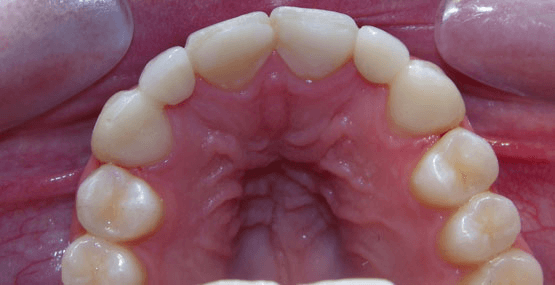

Ultimately, we chose to do two separate bridges out of an all-ceramic material, bonded only to the canines on each side. E.max lithium disilicate bridges from Ivoclar Vivadent 13-X and X-23, cemented by first air abrading the teeth, acid etching with Bisco’s Uni-etch 32% H3PO4 (aq) with BAC, and finally bonding in with Calibra Adhesive Resin cement as per recommended protocol. The results showcase a much more natural smile that’s both brighter and more resilient.